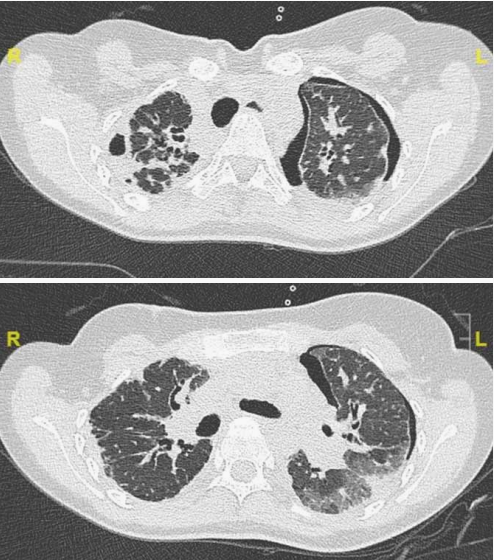

PAP患者症状不典型,诊断主要依据影像学及组织病理结果。胸部影像学特别是出现磨玻璃影、地图征、铺路石征等典型表现需高度怀疑 PAP(图1),但需要和肺水肿

图1 a&b 37岁PAP患者的CT和胸片(同一日期)。a.铺路石征;b.双肺实变。c&d同一患者的支气管肺泡灌洗(bronchoalveolar lavage, BAL)。c.典型的BAL,呈乳白色外观。d.BAL细胞学表现为泡沫状巨噬细胞、细胞碎屑和PAS阳性细胞外小体。